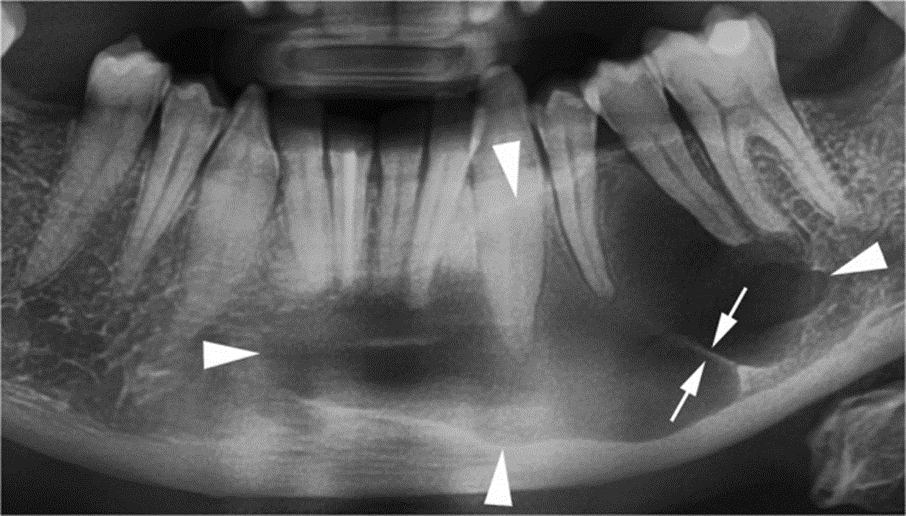

Radiographically, OKCs appear as a well-defined unilocular or multilocular radiolucency bounded by corticated margins (Figure. 1). Unilocular lesions are predominant, whereas the multilocular variant is observed in approximately 30% of cases, most commonly in the mandible (Figure. 1b) [9, 29]. On panoramic radiography, mandibular unilocular OKCs may show few and incomplete septa within the lesions; this finding is more common in larger than in smaller OKCs (Figure. 2).

Cropped panoramic radiograph shows a large OKC with well-defined and lobulated margins (arrowheads) occupying the body of the mandible. Note an incomplete internal septum within the lesion (opposing arrows)

Approximately 30% of OKCs are associated with at least one unerupted tooth, most commonly the third molars (Figure. 1a) [9, 29]. This association occurs particularly in younger patients [15].